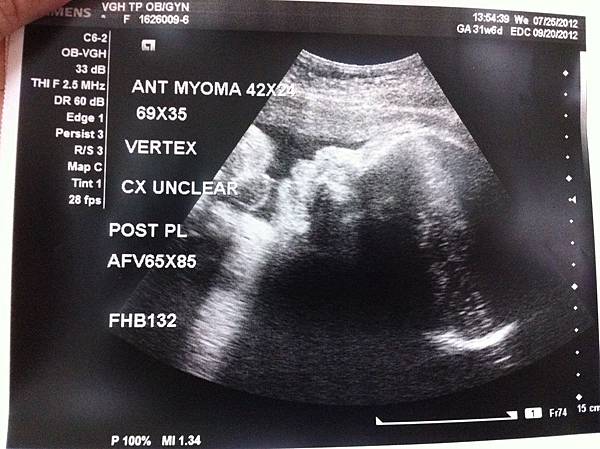

小寶已經30週了,

目前體重1800克,

醫生說一切都非常健康,就是頭很大...